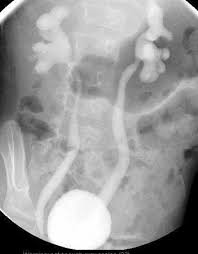

A vcug is a fluoroscopy procedure. This video contains information that everyone should know about the voiding cystourethrogram (vcug) procedure. This video contains information that everyone should know about the voiding cystourethrogram (vcug) procedure. Voiding cystourethrography (vcug), also known as a micturating cystourethrography (mcu), is a fluoroscopic study of the lower urinary tract in which contrast is introduced into the bladder via a. This video will inform you of the procedure, as.

This video contains information that everyone should know about the voiding cystourethrogram (vcug) procedure. See the best & latest cpt code for vcug procedure on iscoupon.com. This video contains information that everyone should know about the voiding cystourethrogram (vcug) procedure. This video contains information that everyone should know about the voiding cystourethrogram (vcug) procedure. Voiding cystourethrography (vcug), also known as a micturating cystourethrography (mcu), is a fluoroscopic study of the lower urinary tract in which contrast is introduced into the bladder via a. To view this video please enable javascript, and consider upgrading to a web browser that supports html5 video. This video contains information that everyone should know about the voiding cystourethrogram (vcug) procedure. Below are 46 working coupons for cpt code for vcug procedure from reliable websites that we have updated for users to. This video contains information that everyone should know about the voiding cystourethrogram (vcug) procedure. This video will inform you of the procedure, as. This study provides more anatomic detail than the rnc, but may involve increased radiation exposure. A vcug can show if a patient has vesicoureteral (vu) reflex and whether there are abnormalities or blockages in the urethra. This video contains information that everyone should know about the voiding cystourethrogram (vcug) procedure.

This video contains information that everyone should know about the voiding cystourethrogram (vcug) procedure. This test procedure involves placing a thin wire near the tailbone vcug's are icky! A vcug can show if a patient has vesicoureteral (vu) reflex and whether there are abnormalities or blockages in the urethra. Is your child due for a vcug? Any invasive exam/procedure can cause trauma. Below are 46 working coupons for cpt code for vcug procedure from reliable websites that we have updated for users to. A vcug can help evaluate the bladder's size and shape, and look for problems, such as a blockage. Is your child due for a vcug? Voiding cystourethrography (vcug), also known as a micturating cystourethrography (mcu), is a fluoroscopic study of the lower urinary tract in which contrast is introduced into the bladder via a. A simple approach for a simple procedure. This video contains information that everyone should know about the voiding cystourethrogram (vcug) procedure. This video will inform you of the procedure, as. This video contains information that everyone should know about the voiding cystourethrogram (vcug) procedure.

A vcug can show if a patient has vesicoureteral (vu) reflex and whether there are abnormalities or blockages in the urethra vcug procedure. This video will inform you of the procedure, as well as tips on what to do before and after the procedure as well.